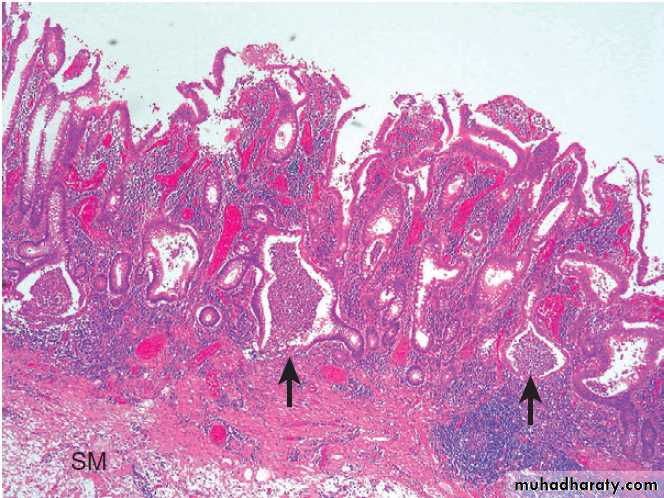

pre-malignant, the normal squamous lining of the lower oesophagus is replaced by columnar mucosa (columnar lined oesophagus( CLO)) that may contain areas of intestinal metaplasia .

Diagnosis. This requires multiple systematic biopsies to

detect intestinal metaplasia and/or dysplasia.

Neither potent acid suppression nor antireflux surgery stops progression of CLO, and treatment is only indicated for symptoms of reflux or complications, such as stricture. Endoscopic therapies, radiofrequency ablation or photodynamic therapy, can induce regression but, at present, are used only for those with dysplasia or intramucosal cancer. Regular endoscopic surveillance can detect dysplasia at an early stage and may improve survival but, because most CLO is undetected until cancer develops, surveillance strategies are unlikely to influence the overall mortality rate of oesophageal cancer.

Surveillance is expensive and cost-effectiveness studies have been conflicting, but it is currently recommended that patients with CLO without dysplasia should undergo endoscopy at 3–5-yearly intervals and those with lowgrade dysplasia at 6–12-monthly intervals.